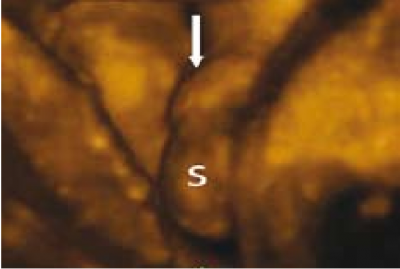

Hypospadias - לעיתים הרמז היחיד לקיום היפוספאדיאס הוא הדגמת Genital tubercle מכוון כלפי מטה, מה שמעיד על עובר ממין נקבה בשבועות 13–16 ובשלב יותר מאוחר הדגמת איברי מין של זכר[34][38]. הכיוון כלפי מטה של איבר המין הזכרי במקרים של היפוספאדיאס הוא כתוצאה מהיווצרות "chordee", שהוא בעצם אטרזיה של הגוף הספוגי (Corpus spongiosum) דיסטלית להיפוספאדיאס. ממצאים סונוגרפיים אחרים שיכולים לרמוז על קיום היפוספאדיאס כוללים: מורפולוגיה לא תקינה של של החלק הדיסטלי של הפין, שני קווים אקוגיניים אורכיים שמייצגים שני הקפלים הלטרליים של שארית העורלה, כיפוף קדמי של הפין, זרם שתן שמקורו מהחלק הונטרלי של הפין[30][39]. וה-"tulip sign" כפי שתואר על ידי מייזנר וחבריו[40] שמייצג בעצם את הכיפוף הפנימי של הפין עם שק האשכים החצוי. אולטרסאונד תלת ממדי יכול להדגים את הכיפוף הפנימי של הפין והיחס שלו לשק האשכים (תמונה 9). אישור סופי לקיום ההיפוספאדיאס ומיקומו ניתן להשגה על ידי הדגמת מקור זרם השתן (תמונה 10) בהשוואה להשתנה תקינה (תמונה 11 ו-12).